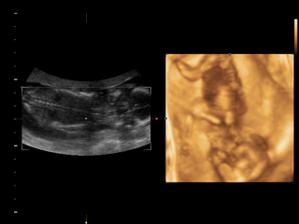

18.10.2010 Naše prďolka se konečně otočil a ukázel se. Pán doktor nám potvrdil,že to bude chlapeček. Nemůžeme si vybrat jméno. Pro holčičku bylo jasné,ale u chlapečka máme problém. Seznam se zůžil na 3 jména. Martin,Daniel a nebo Domink.